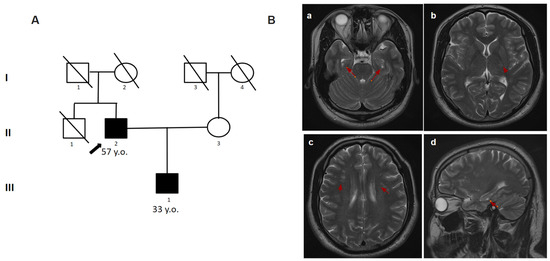

2.4.4. Patient 4.1